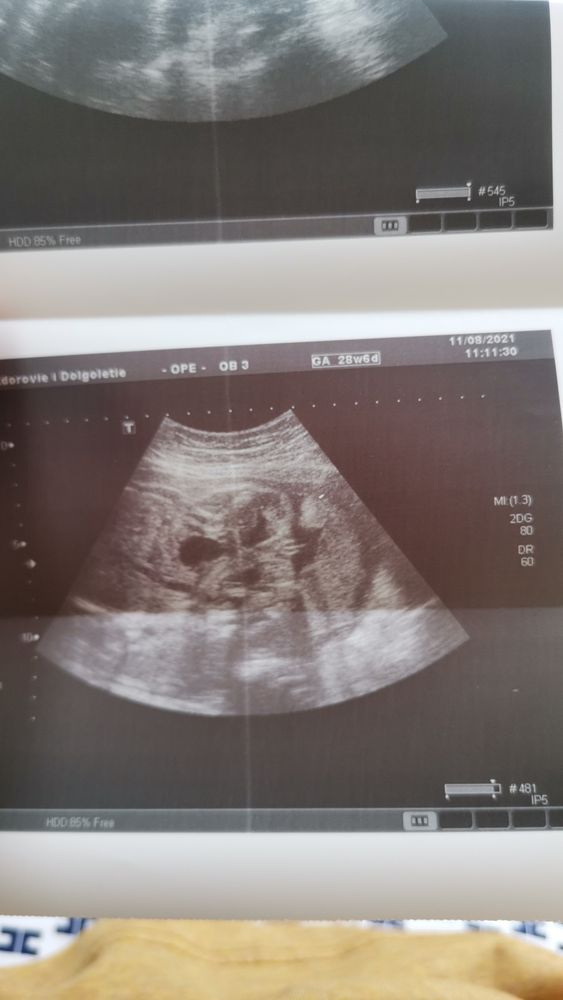

У вас так пуповина проходит,прямо по тому месту, что смазывает картинку. Но больше на мальчишку похоже

Вообще, не поняла, что где на снимке😅

На УЗИ кого предполагают? 29 недель - большой срок, сомнений не должно быть как бы, если ребёнок даёт рассмотреть, конечно.

Юлия Sonnце, вот там где справа в чёрном кружочке говорят что это пися. Но не похоже как то... 🤔

Orlova Marina, никакого кружочка не увидела, извините... Об этой части речь? Обвела.

Orlova Marina, ну, я бы предположила, что это кофейное зернышко. Не очень, по-моему, похоже на мошонку и пенис. У моего в 18 недель уже хорошо так было видно. Вот.

А чем Вас девочка не устраивает, если это она? Так-то, конечно, вернее всего узнать - только в родзале😀